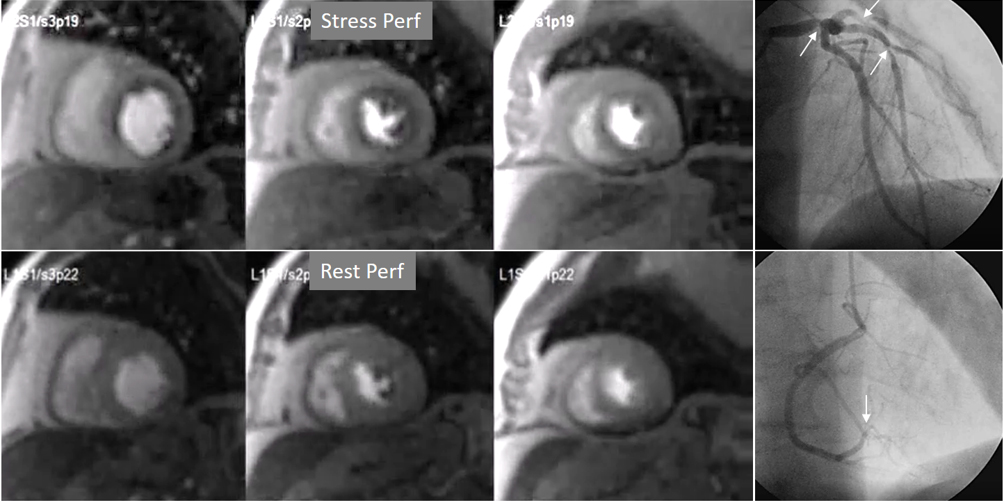

Studies of validation of visually estimated myocardial perfusion CMR for the detection of significant angiographic coronary stenoses started in the early 2000s with encouraging results [63, 64], despite the limited strengths of the images in comparison with current sequences (Fig. 31). Interest in the technique prompted a good deal of studies with a more reliable standard of reference as is invasive FFR, which have been repeatedly submitted to metanalysis [65, 66], showing pooled values of sensitivity and specificity on the range of 0.90. Qualitative perfusion CMR has shown to compare favorably with SPECT for the diagnosis of CAD in the multicenter study MR-IMPACT [67], a finding confirmed in the landmark CE-MARC study [68], from which a strong predictive value of perfusion for events was also shown [69]. The fairly higher spatial resolution of CMR compared with SPECT (2–3 mm vs 10 mm, respectively) may account for these results [68]. The usefulness of Perfusion CMR for risk stratification and prognosis has been also proven in other multicentric studies [70, 71, 72], and even shown to be noninferior to invasive FFR in decision-making upon revascularization in patients with CAD randomly assigned to either CMR or FFR diagnostic strategies [73]. A derived benefit is the favorable cost-effectiveness profile of those protocols where CMR is introduced in the diagnostic workup [74], a finding supported by data from large, “real world” registry data showing advantages in this respect for CMR in comparison with other techniques [75].

Fig. 31.Improving techniques of perfusion sequences. Stress and rest studies with inducible perfusion defects (arrows) in exams performed in the early 2000s (upper row) and currently (lower row). Observe the higher image resolution and contrast-to-noise ratio and the absence of movement artifacts in the current sequence.